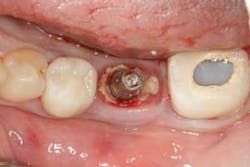

Studies have shown that cement-retained crowns have a higher incidence of peri-implant mucositis (inflammation of the peri-implant soft tissue: Figure 1) and peri-implantitis (inflammation of the peri-implant soft and hard tissue: Figures 2 and 3), likely due to the presence of excess cement following crown cementation. (4) All measures should be taken to avoid the extrusion of excess cement when cementing implant crowns. The use of a radiopaque cement is recommended to detect any excess cement radiographically immediately following cementation (Figure 4). (5) A custom cement analog also can be used to help minimize the chances of excess cement extrusion (Figures 5 and 6). (6)

Figure 2:Abundance of excess cement noted in the peri-implant sulcus once crown was removed.

Figure 3:Note the extent of bone loss around the dental implant induced by the presence of excess cement.